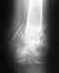

здравствуйте!мне поставили интрамедуллярный гвоздь фиксион! у меня перелом голени!прошло 3 месяца! сделали снимок! сказали,что слабовато мозоль проявляется!скажите пожалуйста,при таком методе (фиксион), мозоль должна сильно проявляться,так же как и в остальных случаях(пластина,например), ввиде бугорков,неких наслоений в месте переломов?